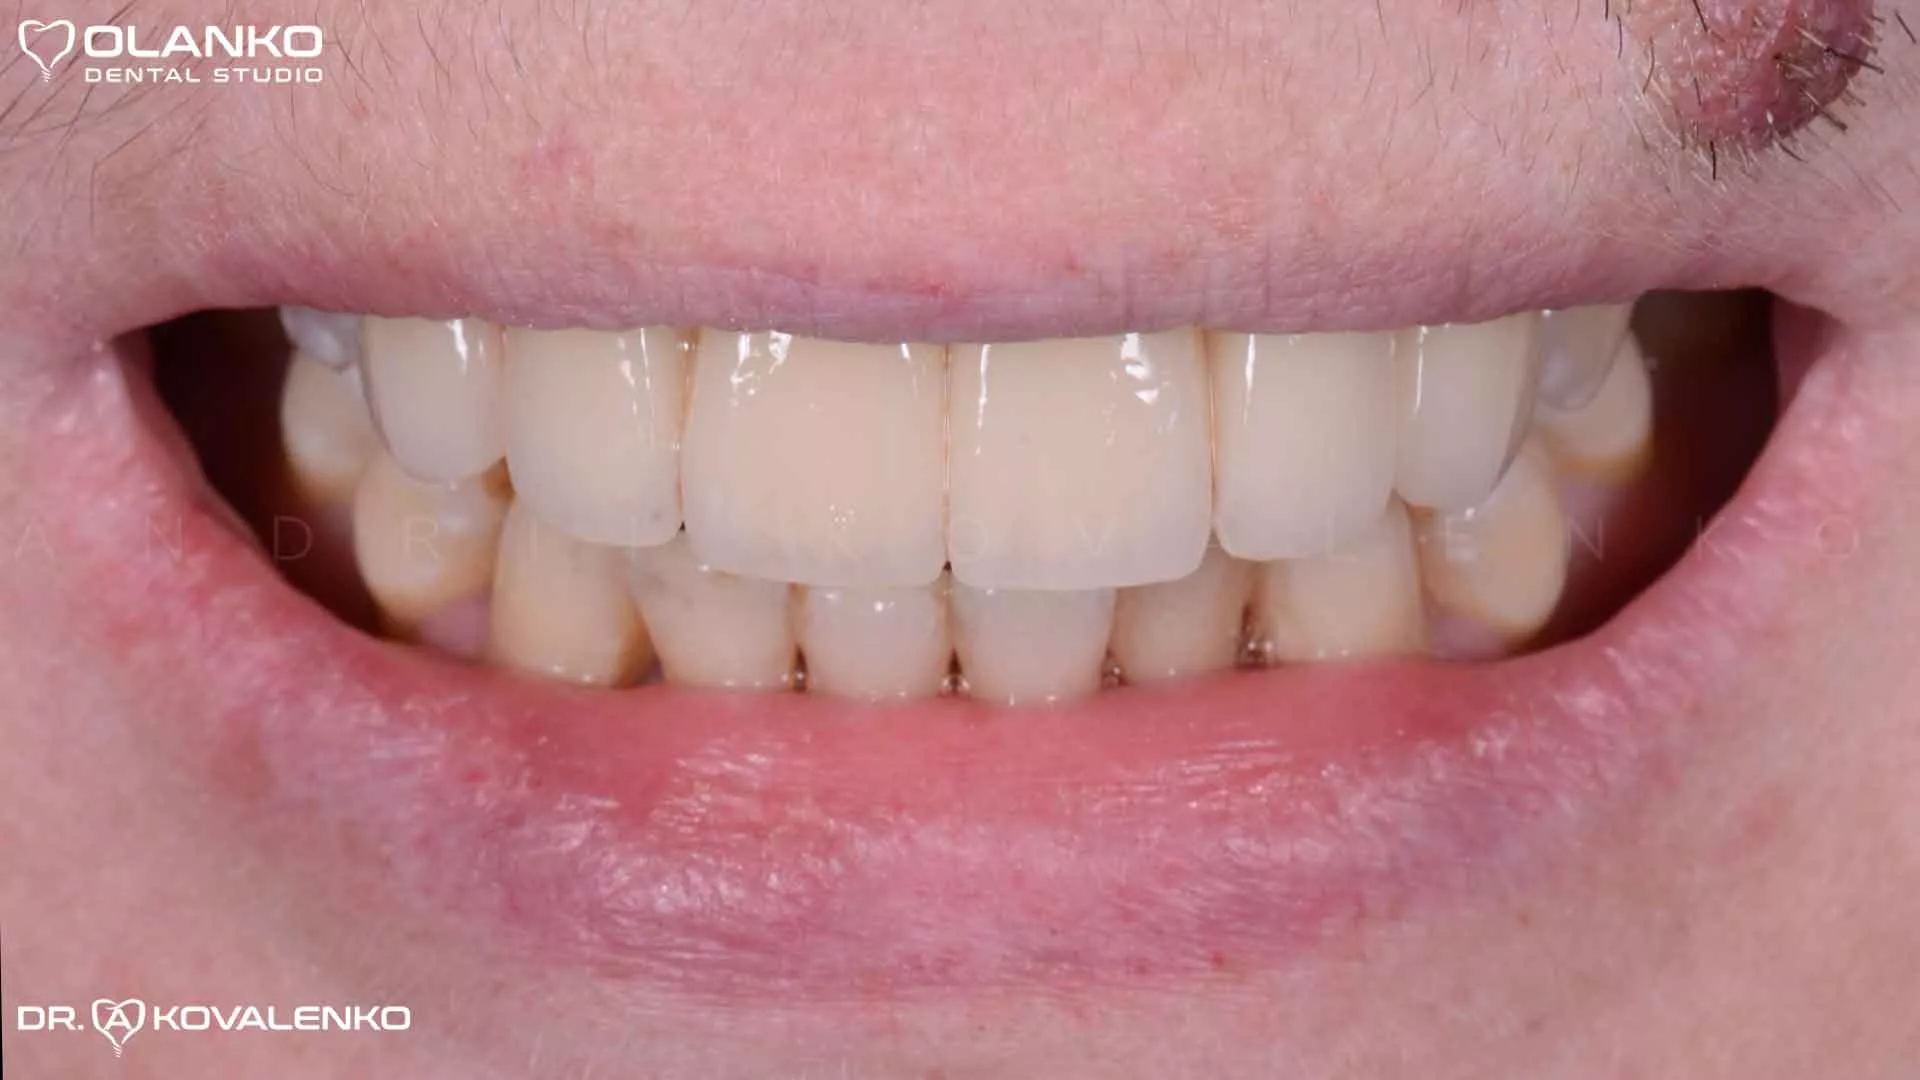

Фото посмішки після установки протеза